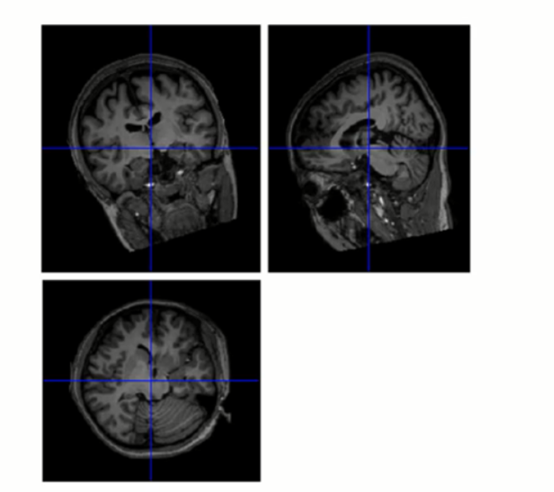

上面两张图所示被试的大脑位置和标准模板是差不多的,如果差得比较多可以通过左下的一系列参数进行调整,另外还需要把蓝色的十字架中心放在前联合的位置(和上图蓝色线所示的位置差不多),以配准原点,这一步直接用鼠标在图上点就可以。右下角QC score是对这个扫描图像的评分/评价,比如这个被试是否长了肿瘤,扫描有没有什么问题等等都可以选择评分,并进行备注,后面会专门生成一个QC文件以方便查看每一个被试的信息。最后按“Reorient image”即会自动跳到下一个被试图像。

这个功能好处是可以一个个被试进行查看并手动调整歪了的图像,但缺点是这一步会在中途直接跳出调整图像的询问窗口,如果不一个个看完就无法进入下一步。当被试太多时,每个功能/结构像都要单独看一遍,消耗的时间较长。因此若手上的数据已经初步看过或已经知道数据基本没有问题的情况下,可以直接跳过这两步。当然如果有被试的图像如下图,与标准模板相差极大,就必须执行手动调整。